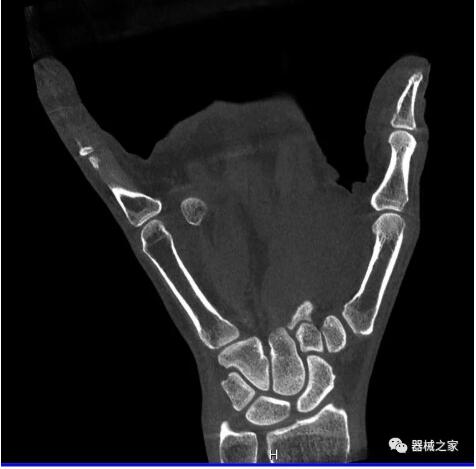

以上介紹的CT均來自國外同一家公司,這些CT均配置了可視化軟件,可以進行切片、3D重建以及大型CT附帶的所有典型的操作功能。

以下是這些“特立獨行”的CT所拍出來的圖像: